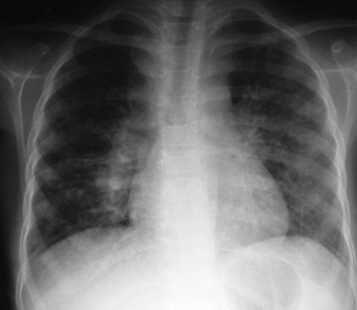

• Sujets identifiés “PNLT (Programme National de Lutte contre la Tuberculose”